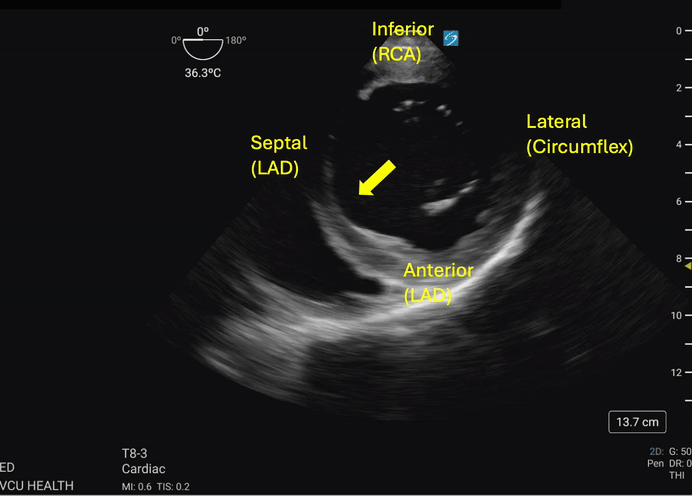

Hypokinesis or akinesis of the left ventricular myocardium segments can indicate tissue ischemia or infarction in specific vascular territories (Figures 3a and 3b). The RCA supplies the myocardium of the inferior wall of the left ventricle. On TEE, the inferior wall is located closest to the probe footprint, since the probe is coming from the stomach located inferior to the heart. The LAD supplies the myocardium of the anterior and septal portions of the left ventricle. The circumflex artery supplies the lateral portion of the left ventricular myocardium and will be shown on the rightward aspect of the ultrasound image.4

Transgastric_Figure_3b_compressed.gifFigure 3b. The septal wall exhibits focal akinesis (arrow) in addition to global hypokinesis which may suggest an acute LAD lesion in the right clinical context. Image courtesy of Lindsay Taylor, MD.